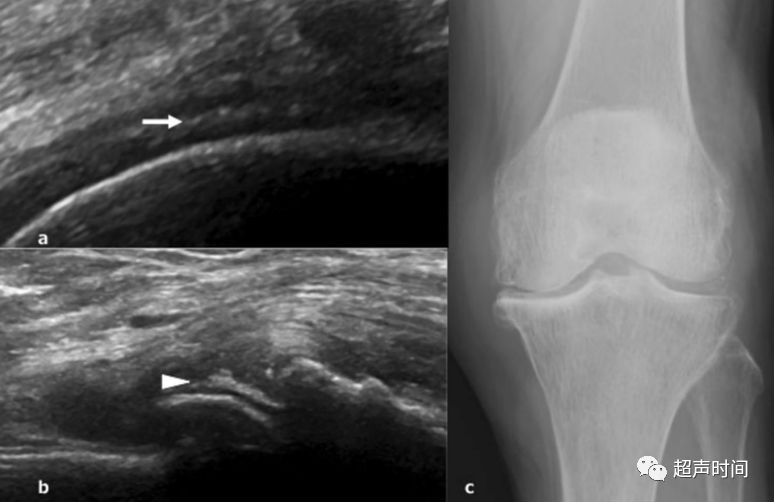

实用干货丨骨关节炎和超声

高分辨率超声诊断骨折

5个病例带你学会足踝部骨折的超声诊断技巧